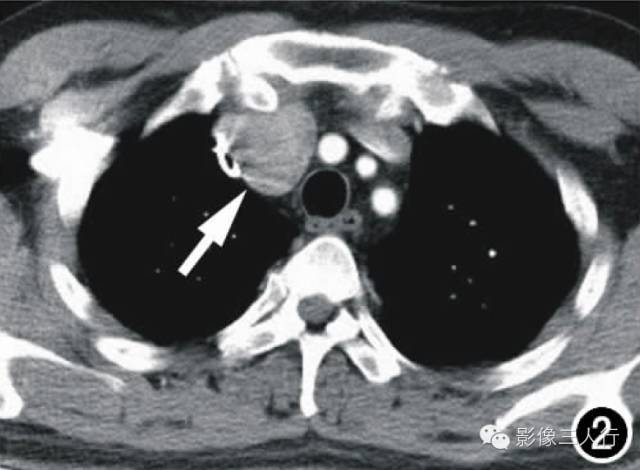

图1横轴面CT平扫示前上纵隔偏右侧一团块影(箭),大小约3.5cmX3.2cm,边界尚清,密度均匀,CT值约44HU,局部血管受压推移。图2横轴面CT增强扫描动脉期示肿块显著均匀强化(箭),CT值为95HU。图3横轴面CT增强扫描延迟期示肿块持续强化(箭),CT值为158HU。图4镜下示细胞排列呈编织状、旋涡状,疏密不均,细胞呈梭形、短圆形,胞核红染,部分细胞出现不典型增生(X400,HE)。